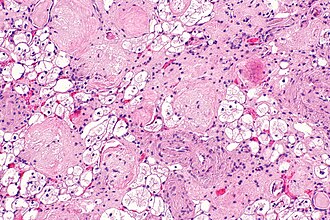

Clear cells in the kidney are commonly seen in tumours and occasionally are seen in benign lesions.

Recognized kidney tumours with clear cells or pale cytoplasm:

- Clear cell renal cell carcinoma.

- Clear cell papillary renal cell tumour (previously clear cell papillary renal cell carcinoma).

- ELOC-mutated renal cell carcinoma.

- RCC with TSC/mTOR pathway mutation.[1]

- Xp11.2 translocation carcinoma.

- Epithelioid angiomyolipoma.[citation needed]

- Multilocular cystic renal neoplasm of low malignant potential.

- Chromophobe renal cell carcinoma - not really "clear" cells.